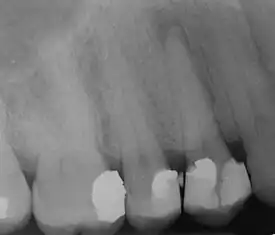

| Radiograph showing bone loss between the two roots of a tooth (black region). The spongy bone has receded due to infection under tooth, reducing the bony support for the tooth. | |

| Diagnostic method | Dental examination, X-rays[1] |

Periodontal disease is generally due to bacteria in the mouth infecting the tissue around the teeth.[5] Factors that increase the risk of disease include smoking,[4] diabetes, HIV/AIDS, family history, high levels of homocysteine in the blood and certain medications.[1] Diagnosis is by inspecting the gum tissue around the teeth both visually and with a probe and X-rays looking for bone loss around the teeth.[1][9]